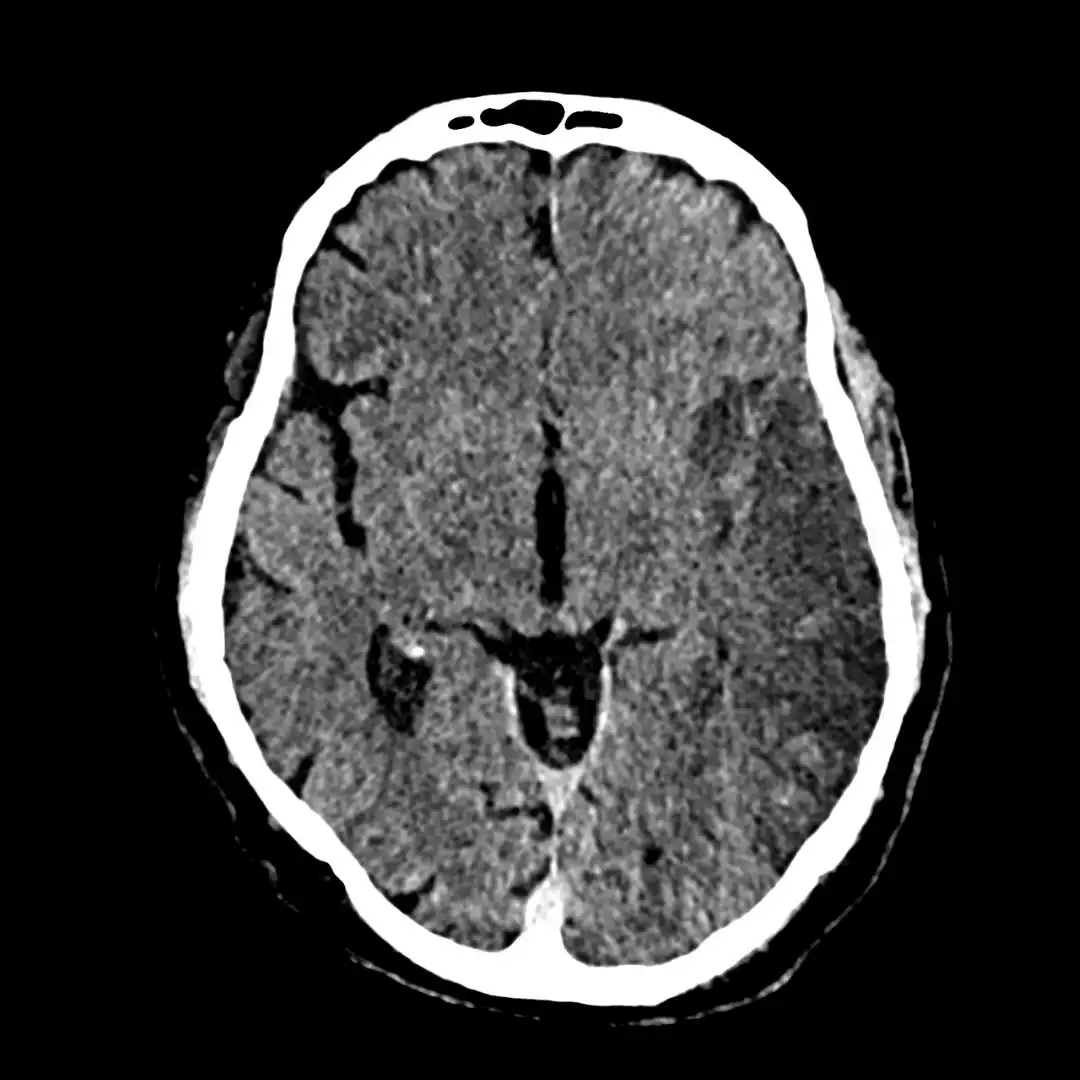

Este curso foi desenvolvido para médicos que precisam interpretar AVC com rapidez, precisão e segurança, dominando desde os sinais iniciais na TC até casos mais complexos, com um conteúdo direto, prático e baseado na experiência real de quem atua diariamente no PS do maior hospital da América Latina, o HC-FMUSP

• Tomografia Computadorizada

Aula 03 – Anatomia Básica: Cérebro Real e a TC

Aula 07 – Como Reconhecer o AVC Agudo e o AVC Crônico

Aula 08 – Sinais Precoces do AVC: Artéria Cerebral Hiperdensa